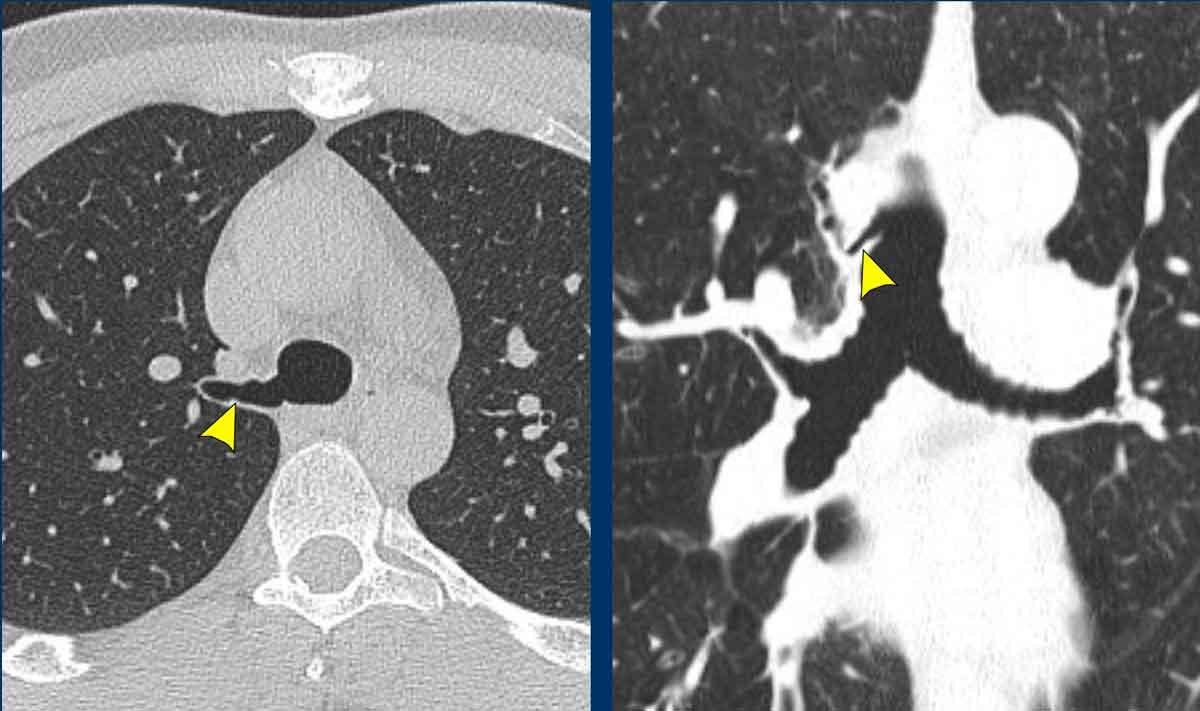

Bệnh u nhú khí-phế quản có tổn thương phổi ở bệnh nhân nam 54 tuổi, cho thấy hai u nhú trong lòng khí quản.

Tiếp tục xem trên cửa sổ phổi…

Hình ảnh cho thấy nhiều tổn thương dạng nang ở cả hai phổi (đầu mũi tên).

Trong một số ít trường hợp, tổn thương có thể lan rộng vào nhu mô phổi, biểu hiện là các nốt dạng nang thường gặp nhất ở các phân thùy đỉnh phụ thuộc trọng lực của thùy dưới. Có một nguy cơ nhỏ về biến đổi ác tính từ u nhú tế bào vảy thành ung thư biểu mô tế bào vảy.